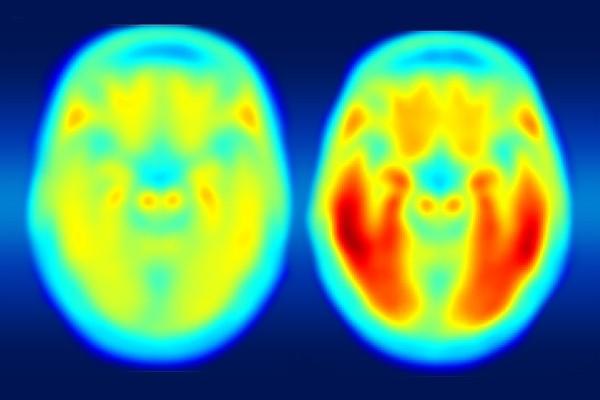

A study using a new PET imaging agent shows that measures of tau protein in the brain more closely track cognitive decline due to Alzheimer's disease compared with long-studied measures of amyloid beta. More red color indicates more tau protein. The image on the left shows the average tau accumulation in the brains of cognitively normal people, averaged over many individuals. The image on the right shows the average amount of tau buildup in the brains of multiple people with mild Alzheimer's symptoms. Scanning multiple individuals shows that the intensity of tau deposits correlates with the severity of cognitive dysfunction. Image courtesy of Matthew R. Brier.

Using a new imaging agent that binds to tau protein and makes it visible in positron emission tomography (PET) scans, scientists at Washington University School of Medicine in St. Louis have shown that measures of tau are better markers of the cognitive decline characteristic of Alzheimer’s than measures of amyloid beta seen in PET scans.

Comparing brain images of people who are cognitively normal to patients with mild Alzheimer’s disease, the researchers found that measures of tau better predict symptoms of dementia than measures of amyloid beta. To determine degrees of cognitive impairment, some of the participants who underwent brain imaging also were assessed with the traditional clinical dementia rating (CDR) scale, cerebrospinal fluid measures, and widely used pen and paper tests of memory and other brain functions.